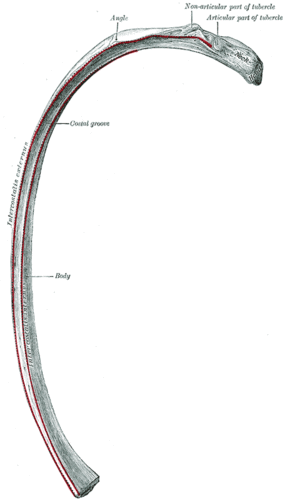

![]() The human rib cage (Source: Gray's Anatomy of the Human Body, 20th ed. 1918) | |

Human ribs are flat bones that form part of the rib cage to help protect internal organs. Humans usually have 24 ribs, in 12 pairs.[2] 1 in 500 people have an extra rib known as a cervical rib. People may have a cervical rib on the right, left or both sides.[3] All are attached at the back to the thoracic vertebrae and are numbered from 1 to 12 according to the vertebrae to which they attach. The first rib is attached to thoracic vertebra 1 (T1). At the front of the body, most of the ribs are joined by costal cartilage to the sternum. Ribs connect to vertebrae at the costovertebral joints.[4]

The first seven sets of ribs, known as "true ribs", are attached to the sternum by the costal cartilages. The first rib is unique and easier to distinguish than other ribs. It is a short, flat, C-shaped bone, and attaches to the manubrium.[6] The vertebral attachment can be found just below the neck at the first thoracic vertebra, and the majority of this bone can be found above the level of the clavicle. Ribs 2 through 7 then become longer and less curved as they progress downwards.[7] The following five sets are known as "false ribs", three of these sharing a common cartilaginous connection to the sternum, while the last two (eleventh and twelfth ribs) are termed floating ribs.[2] They are attached to the vertebrae only, and not to the sternum or cartilage coming off of the sternum.

In general, human ribs increase in length from ribs 1 through 7 and decrease in length again through rib 12. Along with this change in size, the ribs become progressively oblique (slanted) from ribs 1 through 9, then less slanted through rib 12.[7]